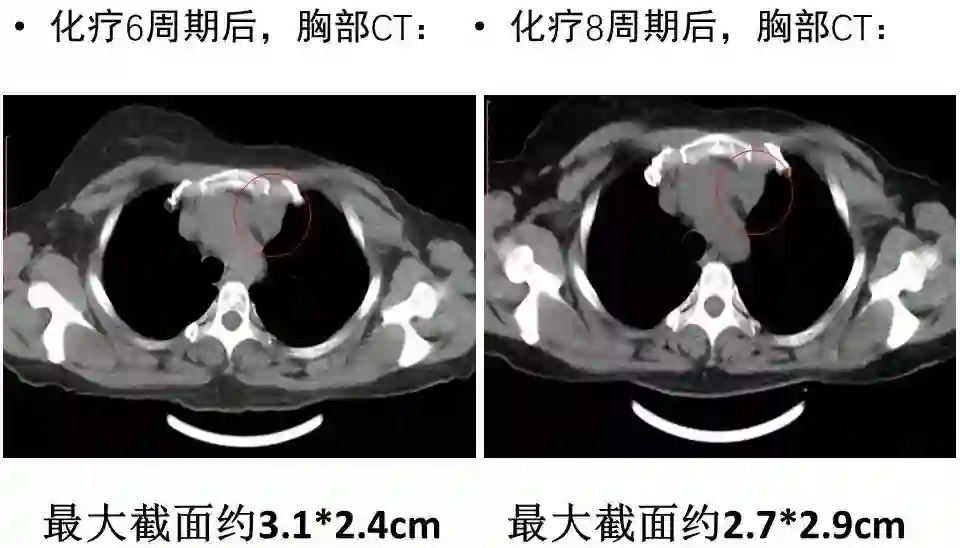

接受TC(卡铂)+曲妥珠单抗单周方案治疗。治疗2个周期后复查:淋巴结彩超示:左锁骨上淋巴结缩小,大的0.6×0.4cm;复查胸部CT示:左侧纵隔肿物缩小,最大截面约6.0×2.9cm。治疗4个周期后再次复查,淋巴结彩超示:左锁骨上淋巴结缩小,大的0.6×0.4cm;复查胸部CT示:左侧纵隔肿物缩小,最大截面约3.1×2.4cm。治疗6个周期后再次复查,淋巴结彩超示:左锁骨上淋巴结缩小,大的0.3×0.3cm;复查胸部CT示:纵膈肿物缩小明显,病灶局部包绕头臂静脉,与胸壁边界不清。评价治疗有效,继续行TC(卡铂)方案化疗+靶向治疗。治疗8周期后再次胸部CT示:纵隔肿瘤缩小明显,最大截面由最初的7.2×2.9cm缩小为2.7×2.9cm,评价为PR。8周期治疗后,患者出现腹泻,大便次数8-10次/天,水样便,影响日常生活,根据NCI分级属3级重度腹泻。10天左右缓解;II度骨髓抑制。患者拒绝继续化疗,曲妥珠单抗改为21天/周期。

图4. 治疗6周期后复查胸部CT平扫

图5. 治疗8周期后复查胸部CT平扫